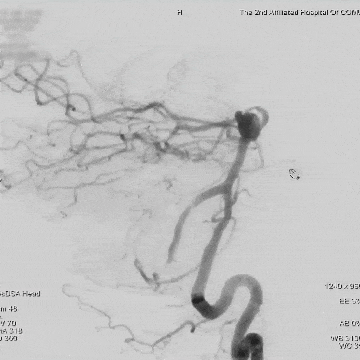

6个月随访:

术后14个月随访:

基底动脉末端动脉瘤不显影,动脉瘤完全闭塞,WEB™完全栓塞。

大脑中动脉瘤充分栓塞,瘤颈残留,WEB™充分栓塞。WEB™被压缩且位置偏转,分支血管有影响。

右侧后交通段动脉瘤完全闭塞。